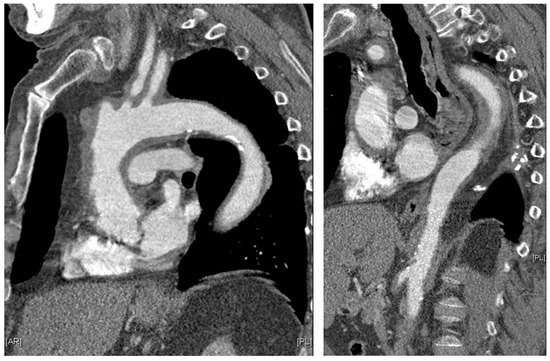

Giant cell arteritis (GCA) affects typically large- and medium-sized arteries, including the carotid arteries and their extracranial branches, as well as the aorta and its branches [48]. Symptoms of GCA include headache, jaw claudication, tenderness of the temporal artery, and low-grade fever [49]. Typical complications of GCA include acute loss of vision and aortic aneurysms, which in turn can lead to more severe complications like stroke or aortic dissection [49,50]. GCA is frequently linked with polymyalgia rheumatica (PMR), characterized by muscle pain and bilateral morning stiffness in the proximal extremities. At a microscopic level, giant cells infiltrate the vascular wall, leading to an occlusion of the affected blood vessels and thus to ischemia of the tissue to be supplied [51]. The diagnosis of PMR/GCA is usually based on clinical presentation, imaging, temporal artery biopsy (Figure 2C,D, Figure 3 and Figure 4), and the ACR/EULAR classification criteria [49,52].

Figure 3. Parasagittal thoracic and sagittal abdominal MPR images on contrast-enhanced computed tomography: pronounced, circular, long-stretch vessel wall thickening of the aorta and its branches in giant cell arteritis. Courtesy of Dr. Corinna Schorn, Rheumatology Center, Rhineland-Palatinate.